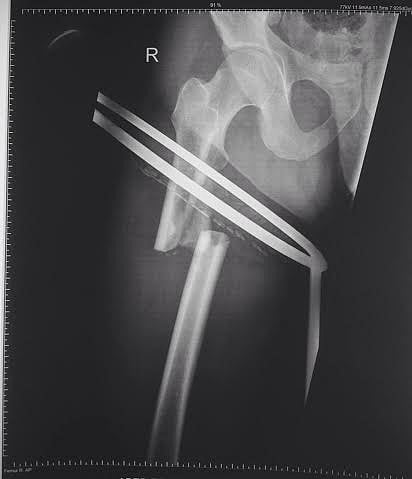

باستخدام تقنية التثبيت بمسمار نخاعي تشابكي

مشاري الحنتوشي- سبق- القويعية: تمكن مستشفى القويعية العام اليوم من إجراء عملية تثبيت كسر في عظم الفخذ باستخدام تقنية التثبيت بمسمار نخاعي تشابكي دون الحاجة إلى إجراء فتح جراحي واسع وذي ألم، في عمليةً تُجرى للمرة الأولى في تاريخ المستشفى.

وأكد مدير العلاقات العامة والإعلام الصحي سعود النداح أن المصاب كان يعاني كسرًا مضاعفًا في الفخذ الأيمن وتقرر تثبيته بمسمار نخاعي تشابكي دون الحاجة إلى إجراء فتح جراحي واسع وذلك بشكل عاجل إذ ضم الفريق الطبي كلاً من: "الاستشاري د . رجب علي ، والاستشاري د. سريان الحتاملة، واختصاصي العظام د. حاتم الغنام".